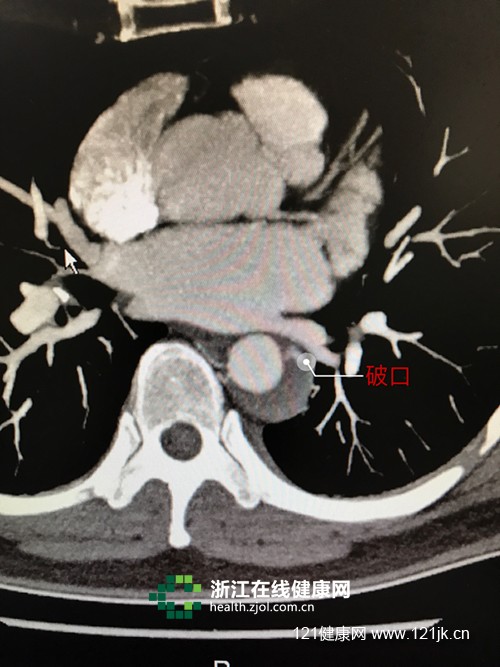

CT片显示主动脉内膜破裂口

医生排除了心肌梗死,但没等郑女士与家人松口气,一个同样十分凶险的病名从医生口中蹦出:心脏主动脉破裂口——主动脉夹层壁间血肿。

医生解释说,主动脉有三层血管壁,主动脉内膜破了,血液从血管腔经破口流入血管中间层,血管壁形成血肿,也就是医学上所称的夹层。如果破口较小或者压力低,可以通过控制血压、心率等,使内膜的破口愈合;若主动脉夹层壁间血肿继续增大,发生主动脉夹层破口,未及时进行手术治疗的话,将危及生命。

经监测,郑女士主动脉夹层壁间血肿在继续增大,浙江省人民医院血管外科主任蒋劲松主任医师为她做了主动脉夹层腔内隔绝术(俗称主动脉放支架),成功“封杀”了具有“不定时炸弹”之称的主动脉夹层。